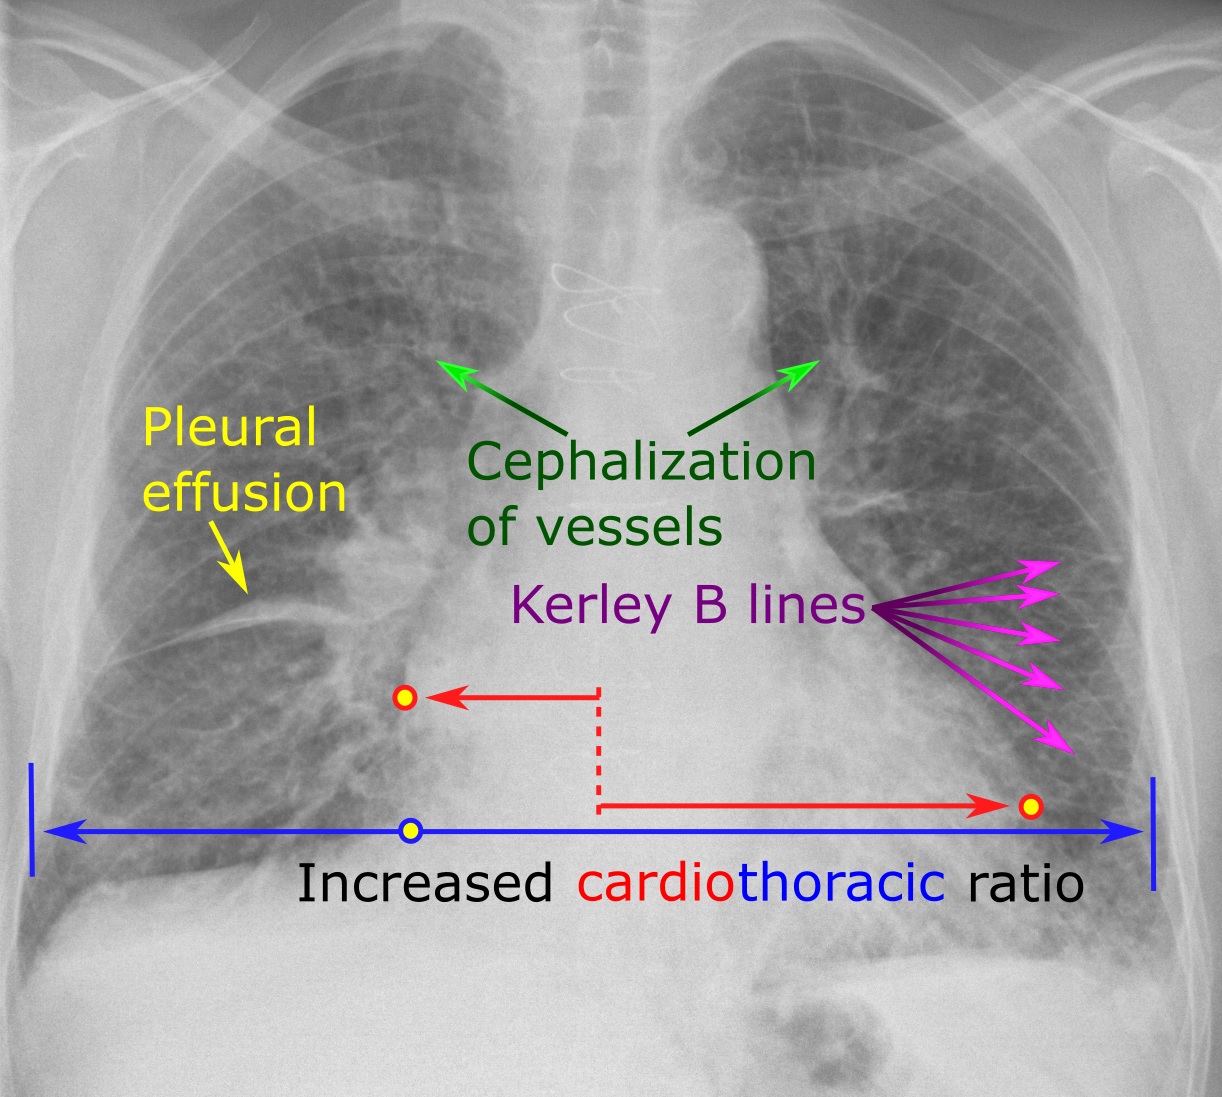

- Chest X-ray – can be used to image any problems or abnormality in lung pathology (e.g. pleural effusions etc).

- Pleural effusion